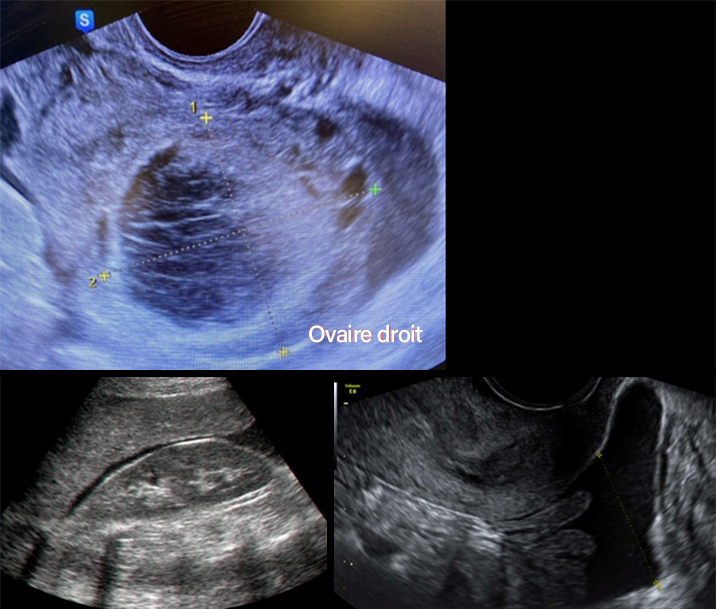

L’échographie pelvienne est la suivante (fig. 4).

Figure 4 (Rodolphe Matias de Sousa, La Revue du Praticien)

Question 6 - Quelle est votre interprétation (une ou plusieurs réponses exactes) ?

Cliniquement, l’hypotension, la tachycardie et les vertiges doivent faire évoquer un saignement actif. À l’échographie, il y a en effet un épanchement abondant dans le cul-de-sac de Douglas remontant jusqu’à l’espace de Morrison.

Une torsion d’annexe correspond à une douleur brutale avec une défense abdominale non soulagée par les antalgiques avec de possibles nausées.

La douleur brutale post-rapport sexuel, l’instabilité hémodynamique, l’aspect d’hémorragie intra-kystique avec cet aspect hétérogène « en toile d’araignée » du kyste et l’hémopéritoine doivent faire évoquer une rupture hémorragique du kyste.

L’instabilité hémodynamique et le caractère probablement encore actif du saignement impose une cœlioscopie exploratrice en urgence.